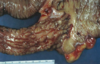

Ischemic Enteritis

A

Ischemic Enteritis

Ischemic Enteritis